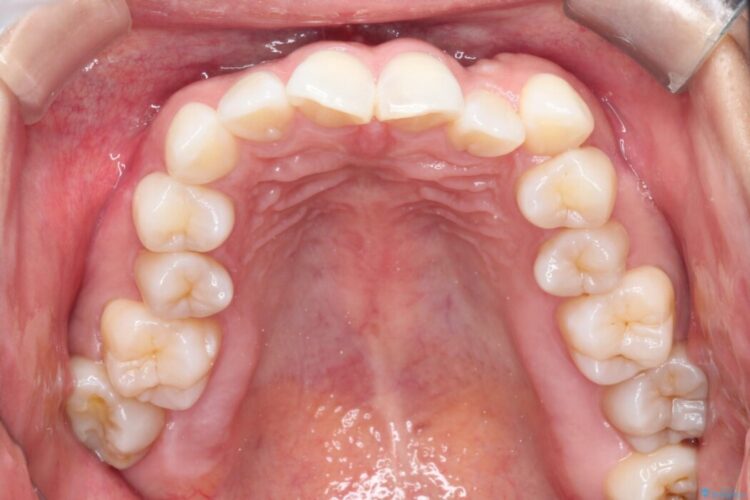

上下のガタつきと、右上の奥歯が外側に飛び出して上下が正しく噛み合わないシザーズバイトの改善のためにご来院された患者様です。

矯正検査の結果、右上7番が頬側に大きくズレており、うまくかみ合っていない状態でした。